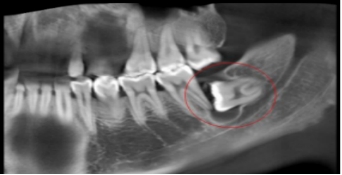

1、反复发作的冠周炎:智齿牙冠周围软组织与牙齿之间形成一盲袋,引起食物、细菌的积存,抵抗力下降时,出现冠周炎症发生。常表现为冠周组织红肿疼痛,以致影响咀嚼,吞咽,还常伴有张口困难及发烧,巴结肿大等全身症状。若炎症未及时控制,还可向颌周、颈部扩散,形成组织间感染、颌骨骨髓炎,甚至还可发生败血症、心包炎等严重全身并发症。

5、邻牙及支持组织的吸收:当阻生的智齿萌出过程中受阻于第二磨牙时,会引发第二磨牙牙根牙根逐渐吸收,严重者可使下颌第二磨牙远中牙根完全吸收,致第二磨牙松动、疼痛,常常食物嵌塞发生慢性牙周炎,也会造成牙槽骨的炎症性吸收,使第二磨牙反复肿痛。